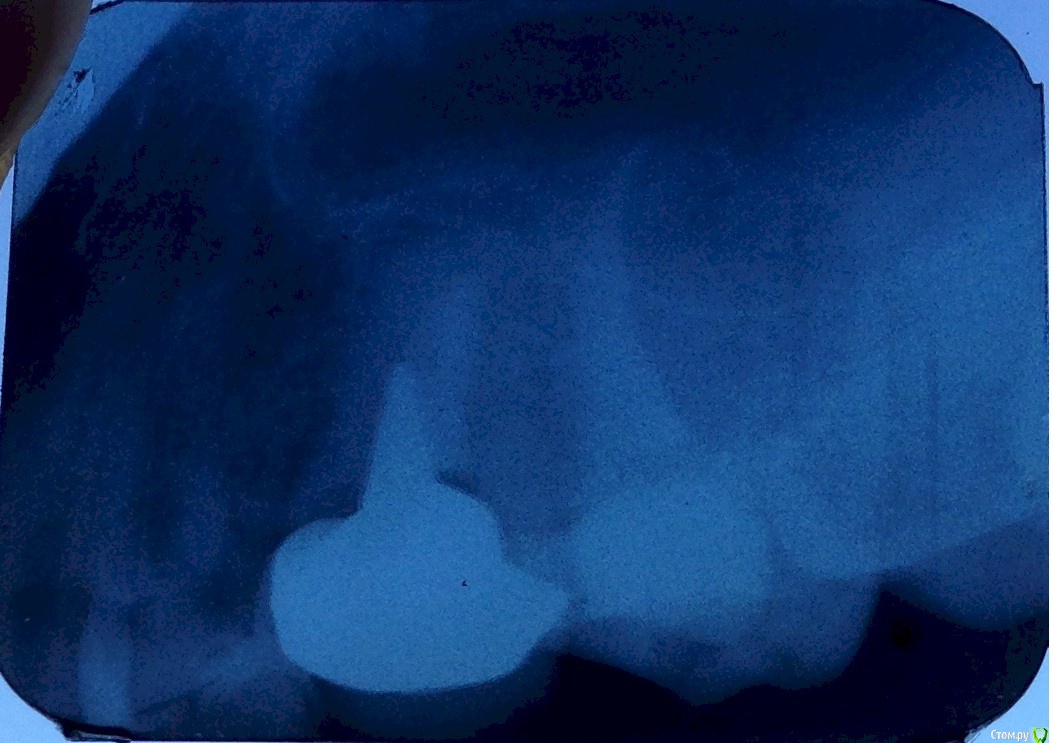

ict Опубликовано 31 июля, 2015 Поделиться Опубликовано 31 июля, 2015 (изменено) Вывалилась вкладка с коронкой на 2.5 зубе через ~16 лет при чистке зуба ниткой. Зуб не беспокоил. У корня зуба по снимку гранулема.Можно и удастся ли распломбировать канал и пролечить гранулему и потом поставить вкладку на место? Какой канал распломбировать?Можно ли приклеить вкладку обратно? Ортопанорама http://s019.radikal.ru/i640/1405/78/25021ba7aea0.jpgЕще снимки http://s018.radikal.ru/i521/1405/71/ec06f3afba06.jpg Изменено 31 июля, 2015 пользователем ict Ссылка на комментарий

ict Опубликовано 7 декабря, 2015 Автор Поделиться Опубликовано 7 декабря, 2015 канал, в котором стояла вкладка перелечивали 4 раза с интервалом в месяц. Снимок показал в конце восстановленение костной ткани. Поставили новую вкладку. Протезист сказал, что стенки тонкие, у внешней стенки где неперелеченный канал небольшая трещина и гарантий не даёт. Никто трещину не видел, увидел протезист. ) Терапевт до этого в этом месте увидел только кариес, который убрал. Протезист предлагал имплант, но я выбрал вкладку. На соседнем жевательном зубе обновил пломбу на боковой поверхности заодно убрав вторичный кариес, так как ее ставили когда стояла коронка и поверхность была волной - пища застревала. Протезист не распознал, что пломба эта новая.Коронку поставили так, чтобы проходила нить между зубами. Я думал, что лучше, чтобы соседние зубы держали коронку впритык. Здоровые зубы ведь стоят впритык друг к другу.Зачем ставят коронки с зазором для нити? Ссылка на комментарий